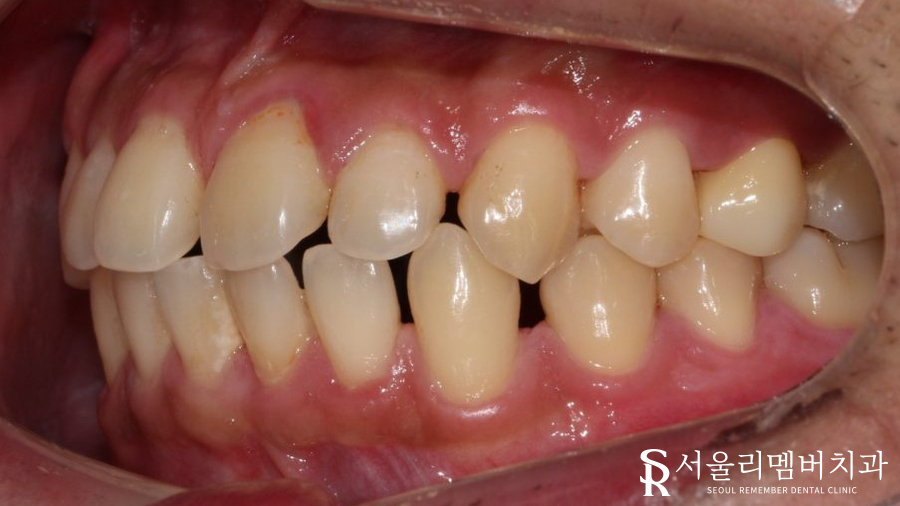

초진 사진을 확인하니,

앞니 사이에 큰 틈이 벌어져 있네요.

생각보다 크게 벌어져 있었기에

레진으로 해결할 수 있을 정도는 아니었습니다.

아래 앞니를 보면

미세하게 벌어져 있는 게 관찰되실까요?